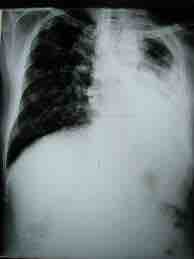

This x-ray of a tuberculosis patient shows the lung on the left side completely infected and the right lung partially infected (the dark areas), with tuberculosis.